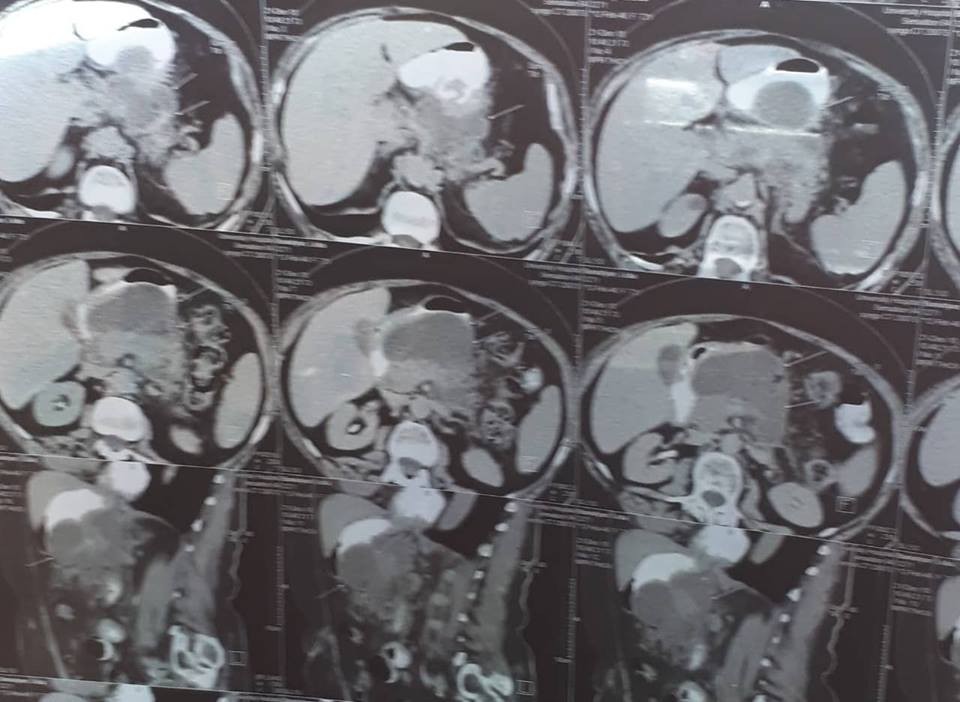

Օրինակ, ՈՒՁ հսկողության տակ դրենավորում կատարել: Առանց կտրվածքների, առանց ընդհանուր անզգայացման: Երեք մեծ թարախակույտ կար, որ հաջողությամբ հեռացրեցինք: Հիվանդը մի քանի օր անց տուն գնաց>>,- պատմում է բժիշկը:

տղամարդը եւ հիպերտենզիա ԱՓՇ-ում…Այս խնդիրների դեպքում բաց վիրահատությունը ուղղակի հակացուցված է: Արա Վարդանյանը ընտրել է այլ ճանապարհ: Առաջին հերթին՝ տեղային անզգայացման պայմաններումուլտրաձայնայինհսկողությամբ իրականացվել է հետորովայնամզային տարածության թարախակույտի դրենավորում, հաջորդ օրը կատարվել է ճարպոնային ծոցի դրենավորում: Սահմանվել է դինամիկ հսկողություն եւ կոնսերվատիվ թերապիա: Ինֆուզիոն, հակաբակտերիալ, սիմպտոմատիկ թերապիան շարունակվել է վիրաբուժական բաժանմունքում: Սրանով, սակայն, բուժումը չի ավարտվել: Մի քանի օր անց դրենավորվել է նաեւ աջից ենթադիաֆրագմալ տարածությունում առկա թարախակույտը: Հիվանդը ստոցիոնարում բուժումը շարունակել է եւս մի քանի օր եւ դուրս գրվել հիվանդանոցից բավարար վիճակում, ճարպոնային ծոցի եւ հետորովայնամզային տարածության գործող դրենաժներով: Նա, իհարկե, կշարունակի մնալբժշկի հսկողության տակ, բայց վերադարձել է նախկին կենսակերպին, ցավային զգացողություններ չունի: